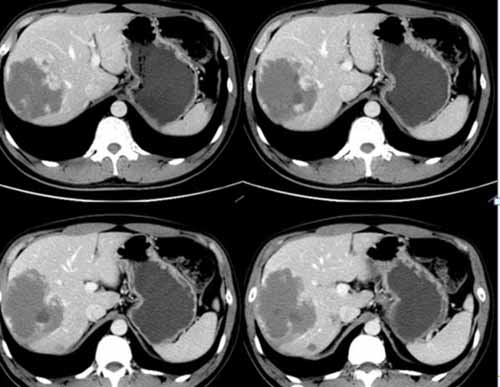

我們來看一個典型病例:

(術(shù)前右肝肝包膜下巨大血管瘤)